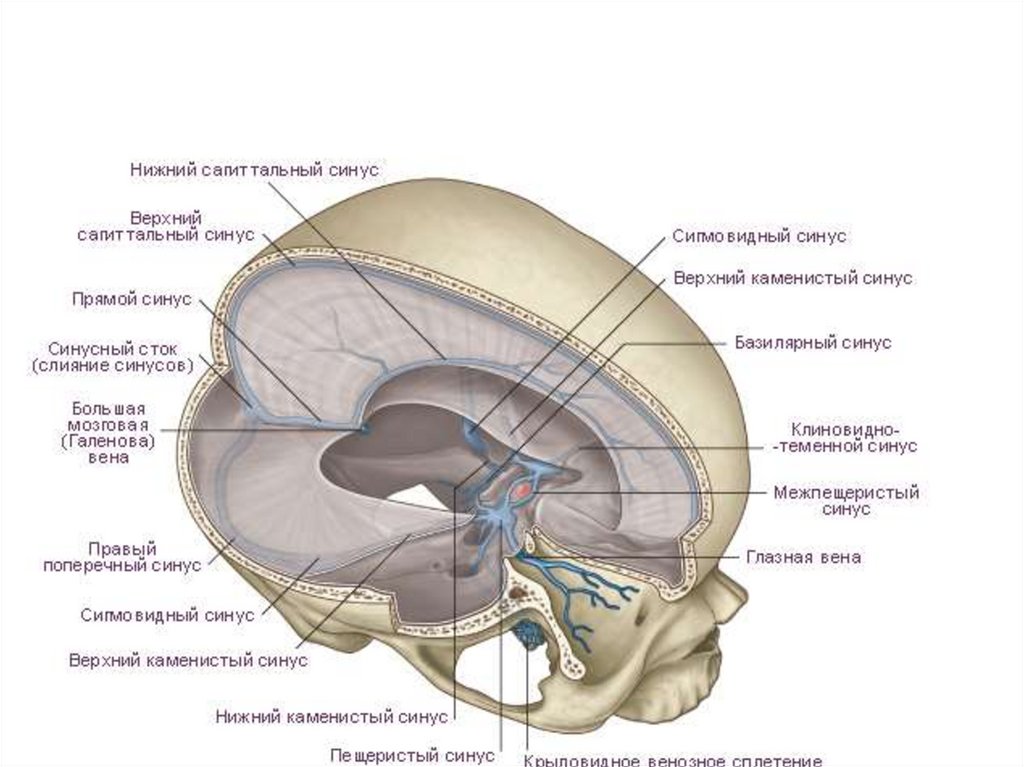

Синусы твердой мозговой оболочки

Кровеносные:

71. Синусы твердой мозговой оболочки